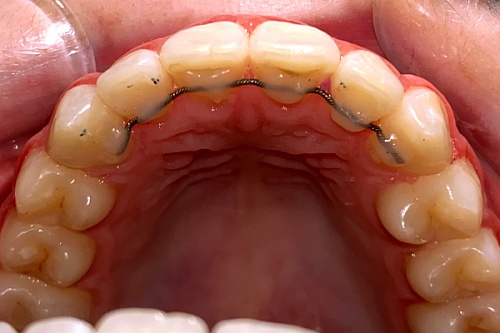

Изменения тканей, которые окружают корни зубов, к сожалению, неизбежны и с возрастом наблюдаются у всех, однако в разном объеме. Так, на развитие пародонтита влияет болезнетворная микрофлора полости рта, которая есть у каждого из нас, но на мы в силах повлиять на ее количество.

Сохранить зубы и пародонт помогает правильная гигиена полости рта дома и в кресле стоматолога, а также своевременное протезирование и имплантация, которые замещают удаленные зубы и равномерно распределяют жевательную нагрузку, не позволяя костной ткани атрофироваться.